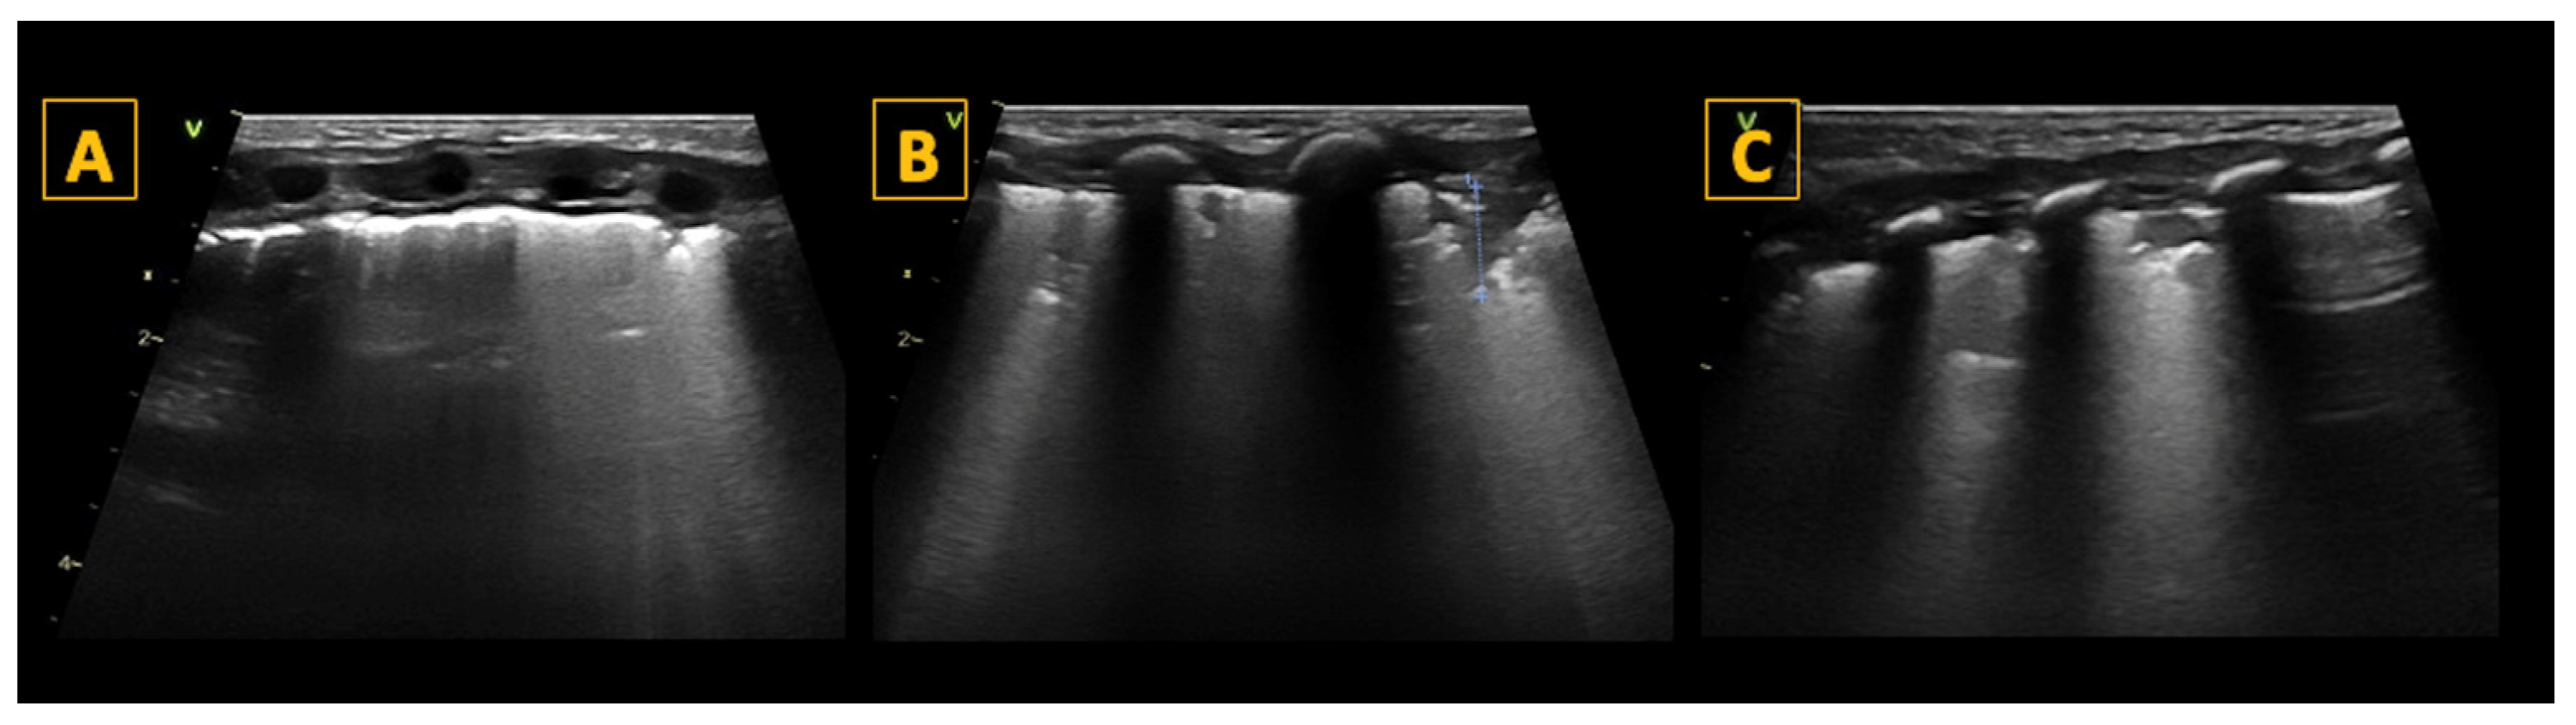

5.4.1. A-Lines

5.4.2. B-Lines